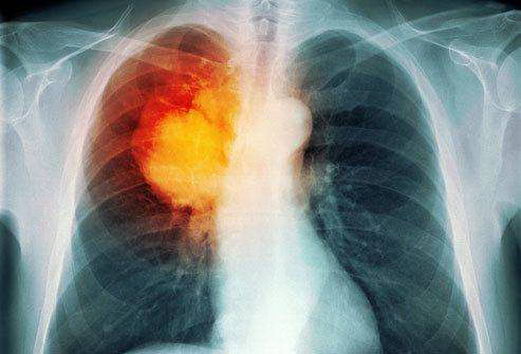

肺癌分为两大类,小细胞肺癌和非小细胞肺癌,针对较常见的非小细胞肺癌而言,医学界将之分为四期,第一、二期的肺肿瘤仍集中于同一面肺部,但当肿瘤入侵至另一边肺部的淋巴结,便属第三期;若扩散至身体其他器官,如常见的骨骼及肝脏,即属第四期。

肺癌多年来是本港的头号癌症杀手,而期数越后,患者的存活率便越低,尤其是第四期肺癌患者,因肿瘤已扩散至肺部以外的器官,医生可用的治疗方案十分有限,被一般人视之为绝症。

幸而,近来就有最新的国际研究指出,将免疫治疗(阿替利组单抗)结合标靶药物(贝伐珠单抗)及化疗的治疗策略,能有助第四期患者延长存活期,而且针对亚洲人常见的EGFR或ALK基因突变型患者的疗效特别显著,为患者延展希望。

目前,尚有不少针对免疫治疗的相关研究在持续进行中,香港临床肿瘤科专科医生李宇聪相信,未来免疫治疗不但有利于非小细胞肺癌的患者,也能惠及小细胞肺癌的病人。